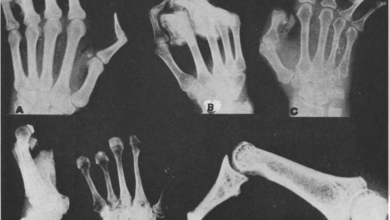

HÌNH ẢNH X QUANG TỔN THƯƠNG XƯƠNG TRÊN BỆNH NHÂN PHONG

Bs. Nguyễn Trung Hiếu 1. ĐẠI CƯƠNG VỀ BỆNH PHONG. Bệnh phong là bệnh nhiễm khuẩn mãn tính do trực…